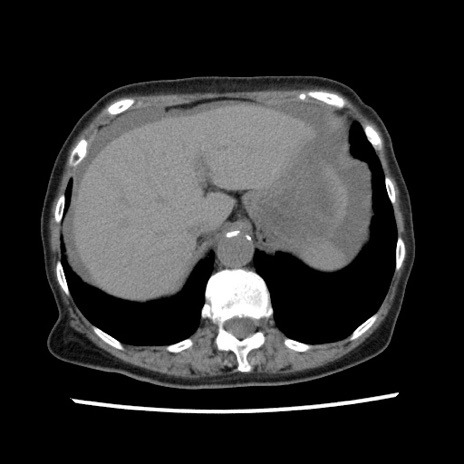

症例1(横断像)

【症例】80歳代女性

【主訴】腹痛

【現病歴】8時間前から腹痛あり来院。

【既往歴】糖尿病、脂質異常症、子宮体癌にて子宮全摘術

【身体所見】意識清明・会話良好だが腹痛で苦悶様、全腹部にわたって反跳痛と圧痛あり

【データ】WBC 13600、CRP 0.14、LDH 224、CK 90